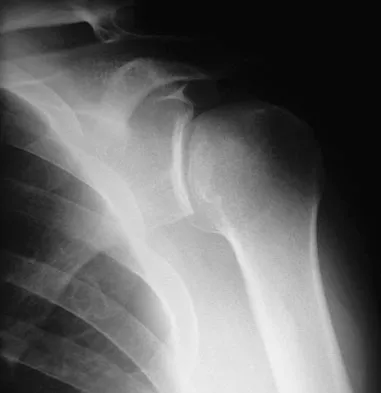

Question 99High Yield

A 50-year-old electrician who is right-hand dominant has had right shoulder pain and stiffness after sustaining an electric shock 2 months ago. An AP radiograph obtained at the time of injury was considered negative, and the patient was diagnosed with a shoulder sprain. The patient now reports continued shoulder pain and restricted motion. AP and axillary radiographs and a CT scan are shown in Figures 41a through 41c. Management should consist of

Explanation